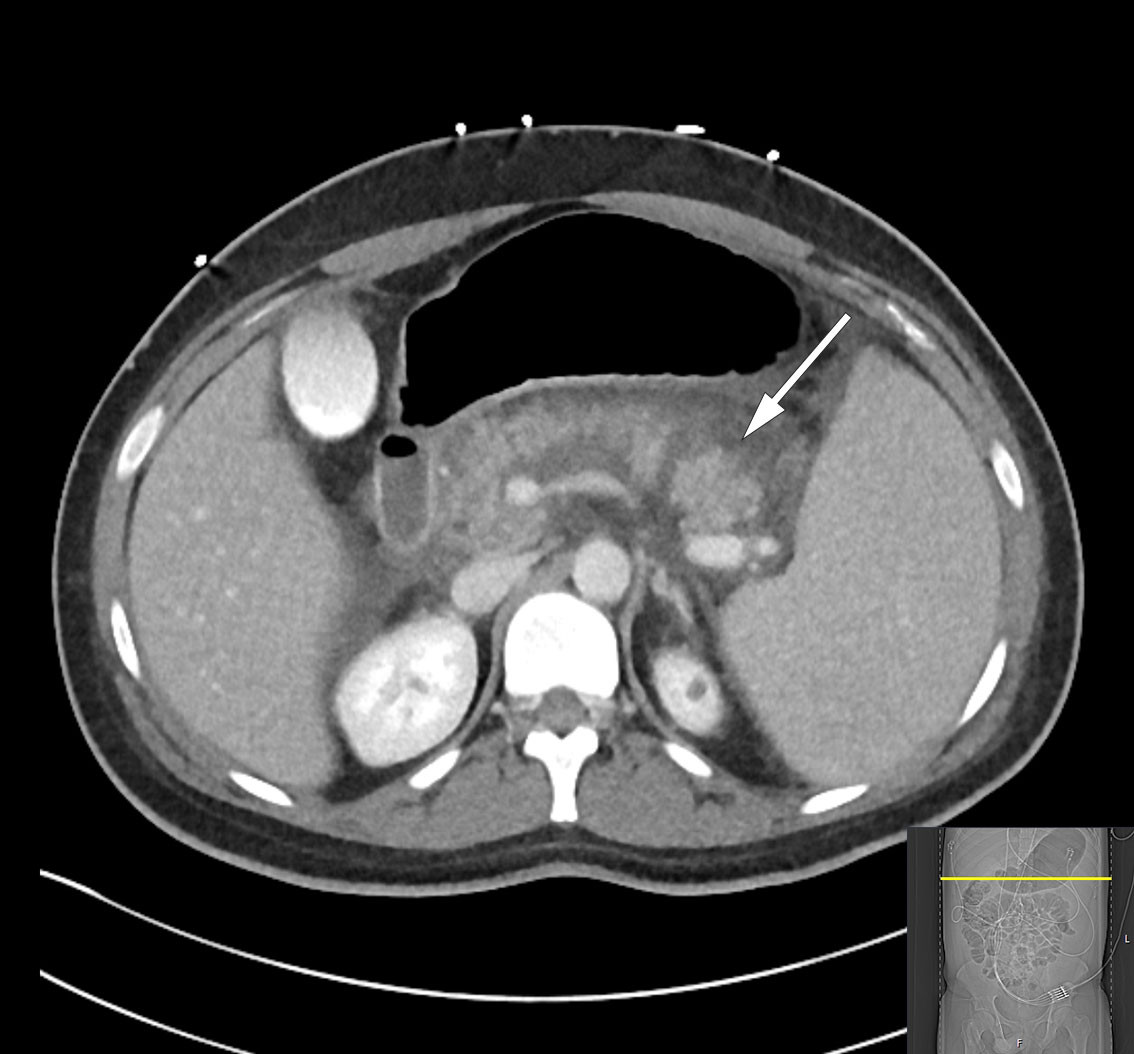

MRCP-undersøkelse samme dag viste peripankreatiske væskeansamlinger og et 4 mm stort konkrement distalt i ductus choledochus (figur 1). I tillegg forelå uttalte pankreatittforandringer med omkringliggende ødem og væskeansamlinger i øvre abdomen. Tredje dag etter innleggelsen var pasienten ytterligere medtatt og smertepåvirket samt plaget av kvalme. Blodprøver viste vedvarende leukocytose på 45,6 × 109/L. CRP-nivået hadde økt til 261 mg/L, og bilirubinnivået hadde steget videre til 290 µmol/L. Det ble startet bredspektret, intravenøs antibiotikabehandling i form av piperacillin/tazobaktam 4 g/0,5 g tre ganger daglig på mistanke om samtidig infeksjon i galleveier. Videre ble pasienten henvist til endoskopisk retrograd kolangiografi (ERC), som ble utført ukomplisert med papillotomi fulgt av fjerning av to sorte konkrementer i distale choledochus. Galleblæren var pakket med konkrementer ved kolangiografi. Det ble i etterkant samme dag målt bilirubinnivå fallende til 139 µmol/L.

Den kliniske tilstanden ble i løpet av tredje døgn ytterligere forverret med sterke magesmerter. Pasienten ble overflyttet til intensivavdeling grunnet begynnende organsvikt med O2-behov. Pasienten var somnolent, men selvpustende, og i behov av 2–3 L O2 på nesekateter for å opprettholde adekvat oksygenmetning > 92 %. Videre forelå stigende INR-verdi på 1,9 samt fallende albuminverdi på 22 g/L (fra 45,6 g/L), som ga mistanke om blødningsforstyrrelse. I tillegg tilkom ny stigning i bilirubinnivå til 290 µmol/L, men i fravær av øvrig stigende nivå av lever- og galleprøver ble behov for ny ERC-undersøkelse avventet etter tverrfaglig diskusjon. Ytterligere diagnostikk med CT av abdomen og bekken viste nekrotiserende pankreatitt med peripankreatiske væskeansamlinger samt fri væske i buken (figur 2). Det var ingen tegn til intra- eller ekstrahepatisk kolestase. Videre forelå bilateral pleuravæske og sammenfalt lungevev, som kunne forklare pasientens respiratoriske forverring. I lys av forhøyet INR-verdi ble det avstått fra pleuratapping. I tillegg ble det bemerket forstørret milt (største lengde 21 cm).